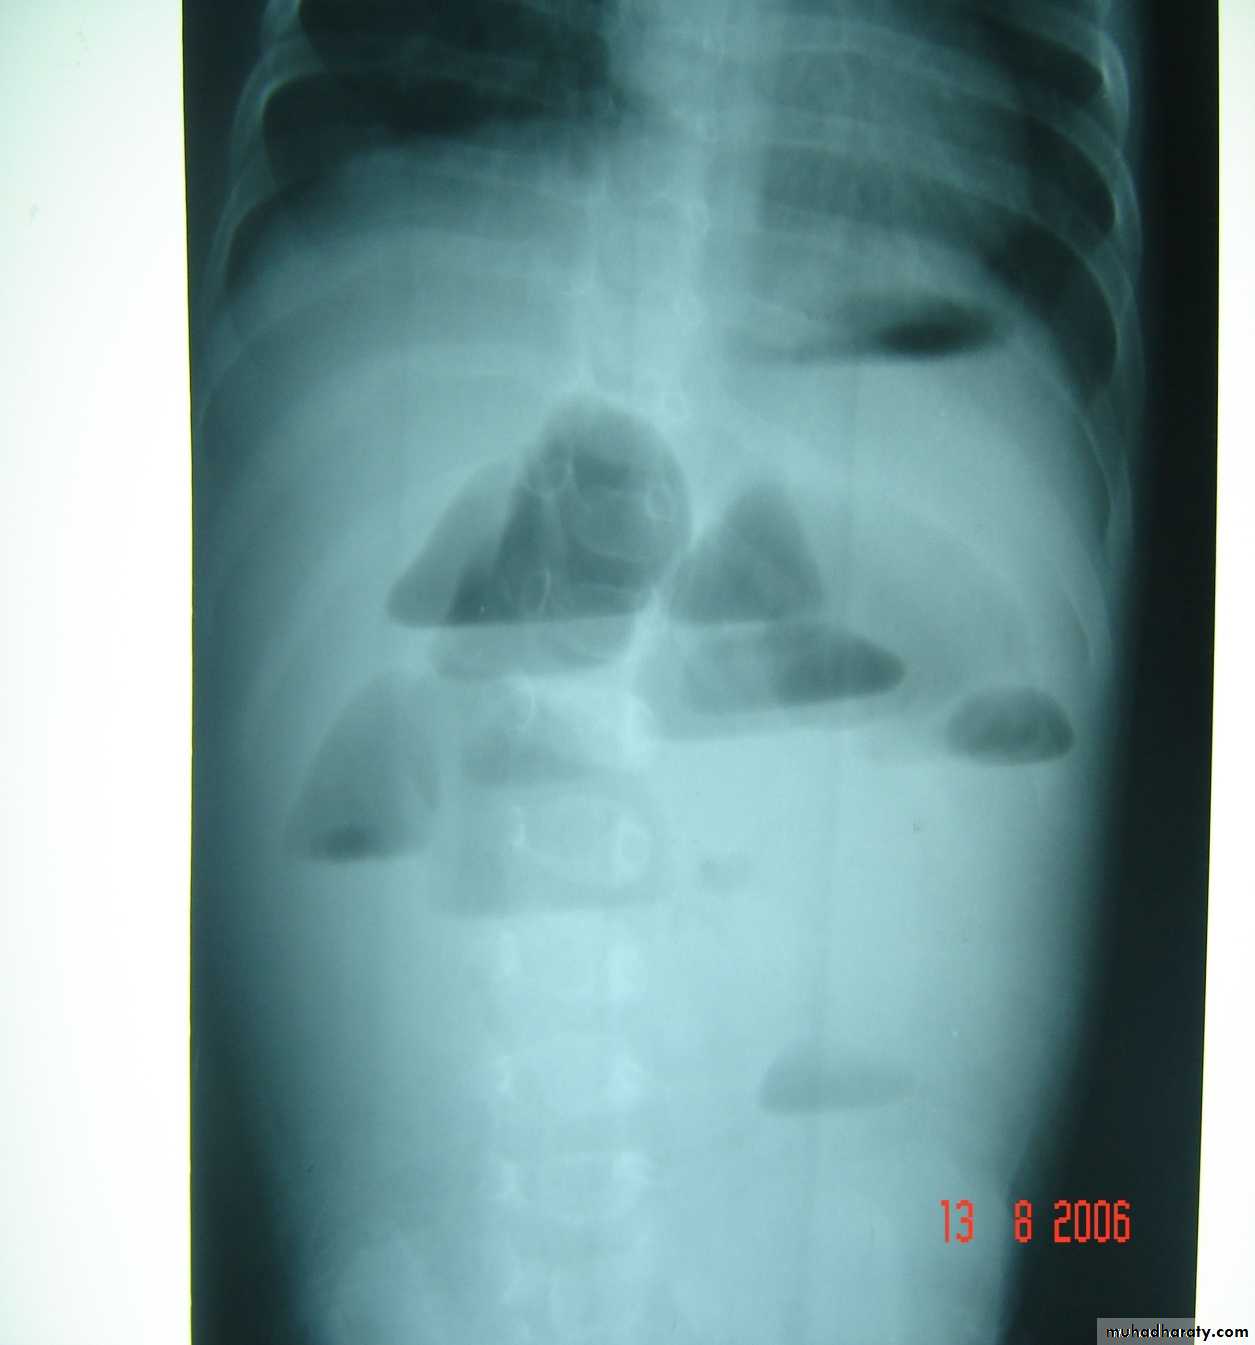

Second photo:

Diagnosis: TEF (with fistula)

Description: pass of gases to the abdomen + failure of nasogastric tube passage.

Diagnosis: TEF (atresia with fistula)

Benefits of X-ray:1- to see the failure of nasogastric tube passage.

2- to determine the type of TEF

3- to check the condition of the lung

4- diagnose the associated anomalies (aortic arch – vertebra – ribs)

5- to measure the length of the defect (1-2-3 cm or more)